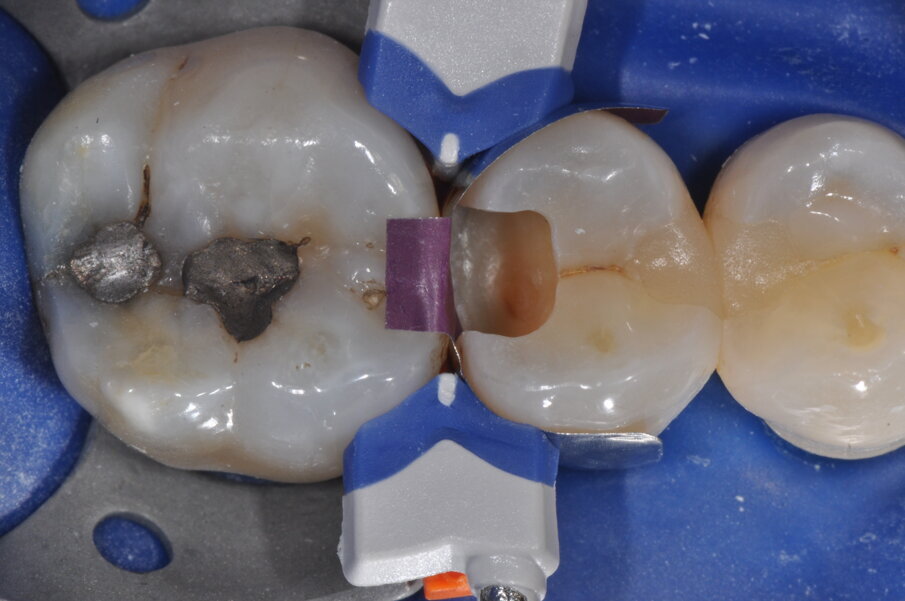

Viene posizionato un cuneo con matrice allo scopo di proteggere il dente aprossimale (Fig. 2). La cavità è stata preparata, la carie asportata, i margini cavitari devono essere rifiniti (Fig. 3). Vengono rimossi il cuneo e la matrice per meglio rifinire il gradino cervicale e per valutare che tipo di cuneo utilizzare (Fig. 4). Ai fini di migliorare l’adattamento della matrice viene utilizzata una striscia abrasiva in plastica di grana media (Fig. 5).

Viene posizionata una matrice Fusion FX175 e inserito un cuneo Fusion FXOR da vestibolare, per favorire la chiusura della matrice nell’angolo tra gradino cervicale e parete assio-pulpare vestibolare, resa difficile dalla rotazione dell’elemento 1.5 (Fig. 6). Si posiziona l’anello separatore FX400 - si noti il perfetto adattamento della matrice alle pareti assiali e al gradino cervicale. Quest’ultimo grazie soprattutto all’azione delle alette in silicone del cuneo (Fig. 7). Un’altra inquadratura evidenzia la profondità della cavità pulita (Fig. 8).